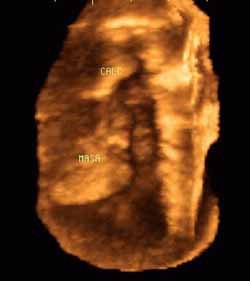

Obstruction of the common bile duct and pancreatic duct by tumoral growth at head of pancreas

A 50-year-old man who developed a greenish jaundice over 15 days, along with general decline in health, was admitted to the ultrasound department for an abdominal scan, assessment of etiology of disease, and treatment. The study showed dilatation of the intrahepatic and extrahepatic bile ducts, with distal obstruction of the common bile duct, tumor at the head of the pancreas, and dilatation of the bile duct and pancreatic duct.

![]() |

| Volumentric reconstructions obtained with 3-D ultrasound (Figure 8a, above) are compared with images obtained using endoscopic retrograde cholangeography (Figure 8b, below). Note the similarity of information that both methods bring to the diagnosis, including tumor at the head of the pancreas, and dilatation of the bile duct and pancreatic duct. |